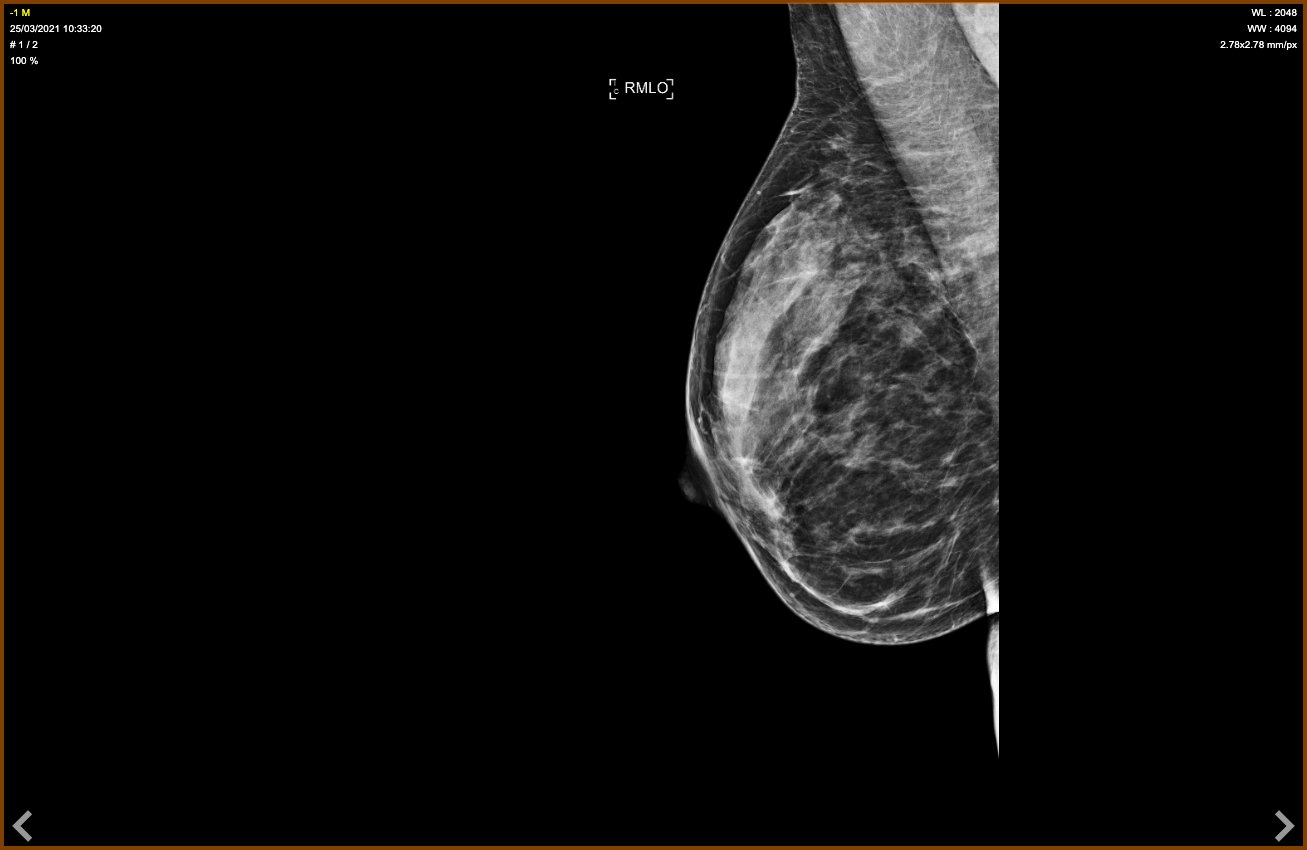

Femme de 47 ans, mammographie de dépistage.

Foyer de microcalcifications de 18 mm poussiéreuses se projetant sur le muscle pectoral à droite BI-RADS 4b, difficile à voir.